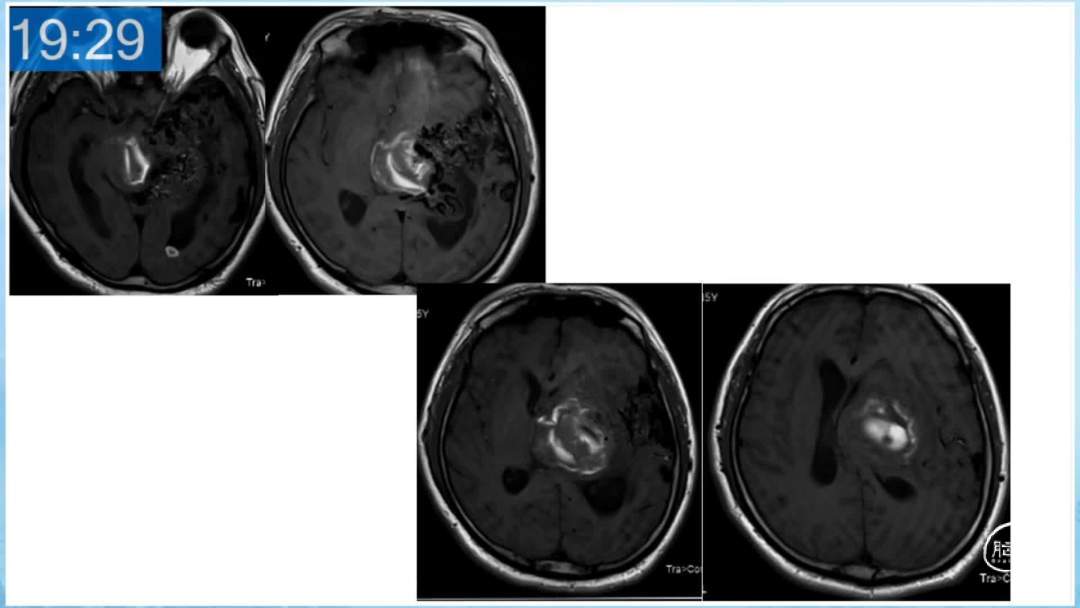

本期为大家特别分享:空军军医大学唐都医院邓剑平教授的精彩会议内容《颅内动静脉畸形的复合手术治疗》,欢迎大家阅读和分享!